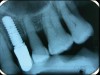

The first step in preventive strategies must be to perform a correct diagnosis of the peri-implant condition by accurately assessing the health of the peri-implant hard and soft tissues through periodontal probing and periapical radiographs at the time of definitive prosthetic installation. These measurements should be considered the baseline diagnosis and, therefore, represent a true starting point for evaluating the changes on the radiographic bone levels and probing pocket depths (PPD) at future recall appointments (Figure 1 and Figure 2).6 Although probing depth measurements of peri-implant tissues do not have the same diagnostic value as probing periodontal tissues, there is evidence that BOP is the most objective sign of peri-implant tissue inflammation; significant deepening of PPD compared with baseline measurements is also a sign of disease that indicates the need to perform a radiographic evaluation (Figure 3 through Figure 5).6,10,11

Fig 1. Baseline measurements at the time of prosthetic delivery: probing pocket depth and

Figure 1

Fig 2. periapical radiographs.

Figure 2